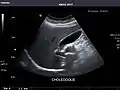

Gallbladder

Bile duct

Gallbladder: No stones, wall thickening, or pericholecystic fluid.

Common Bile Duct: Nondilated measuring 1.3 mm at the level of the porta hepatis.